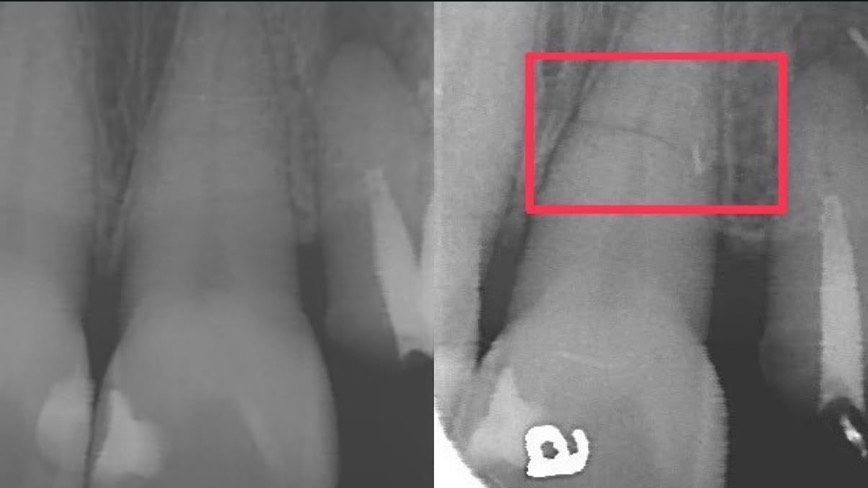

牙裂癥兆通常如牙冠裂會敏感、牙根裂則咬東西會不適。而這個案例是為牙根裂了

以上經兩週後觀察,撞到的牙齒咬合壓診時還是會痛;而後再經過後面兩週時間回診,C小姐還是覺得有點痛,此時去拍了x光片後,就發現有明顯的水平狀牙裂了!

要知道「牙裂」其實是很不容易經由x光片拍出來的,兩個月後明顯拍出了裂痕,所以小編才能特別跟大家分享這個案例唷!